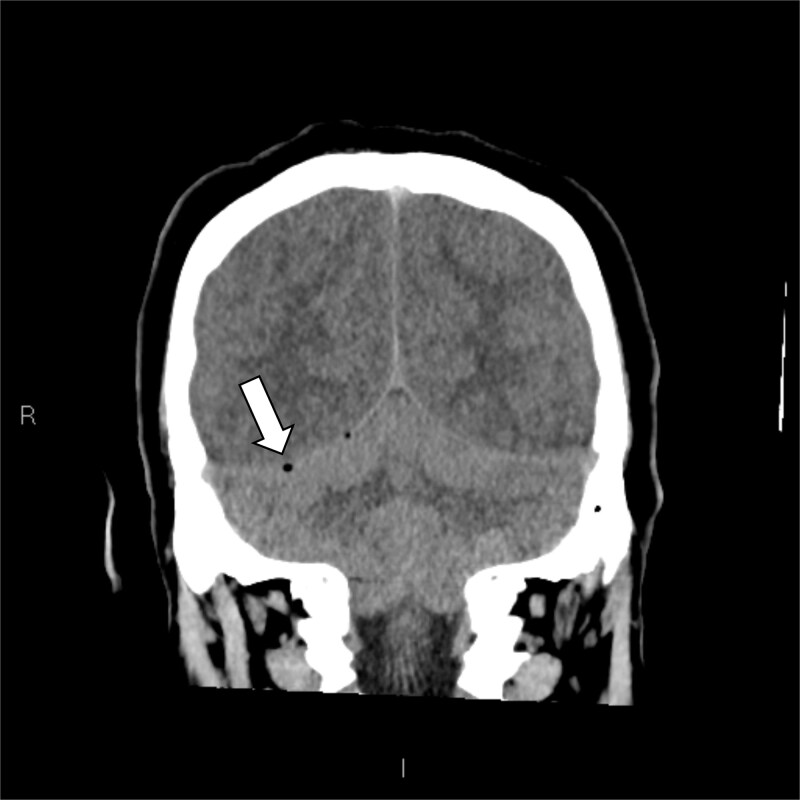

既往健康,免疫功能正常的中年男性,12小时右耳疼痛史,轻度流感样疾病后出院,到地区医院就诊。他的神经系统迅速恶化,瞳孔扩大,癫痫发作,需要插管。在紧急转至第四重症监护室后,多学科评估(耳鼻喉科和神经外科)、神经影像学和右耳鼓膜切开术证实耳瘤乳突炎合并脑静脉窦血栓形成。CT静脉造影显示广泛血栓形成,包括右乙状窦、横窦和上矢状窦。鼓膜切开术显示培养阴性血染脓。肺部微生物学结果对乙型流感和烟曲霉复合体呈阳性。尽管进行了最大限度的医疗治疗,患者还是出现了双侧静脉梗死、脑水肿和小脑扁桃体突出,并在48小时内进展为脑死亡。器官捐赠按照患者先前的意愿进行。即使在健康个体中,耳乳突炎也可引起快速、致命的颅内并发症,因此需要早期影像学检查、专家介入和警惕神经功能衰退。

A previously healthy, middle-aged immunocompetent man presented to a regional hospital with a 12-h history of right ear pain and discharge following a mild flu-like illness. He rapidly deteriorated neurologically, developing dilated pupils and seizures requiring intubation. Following urgent transfer to a quaternary ICU, multidisciplinary assessment (ENT and Neurosurgery), neuroimaging, and right ear myringotomy confirmed Otomastoiditis with catastrophic cerebral venous sinus thrombosis. CT venography demonstrated extensive thrombosis involving the right sigmoid, transverse, and superior sagittal sinuses. Myringotomy revealed culture-negative blood-stained pus. Pulmonary microbiology results were positive for Influenzae B and the Aspergillus fumigatus complex. Despite maximal medical management, the patient developed bilateral venous infarctions, cerebral edema, and cerebellar tonsillar herniation, progressing to brain death within 48 h. Organ donation proceeded in accordance with his prior wishes. Otomastoiditis can cause rapid, fatal intracranial complications even in healthy individuals, highlighting the need for early imaging, specialist input, and vigilance for neurological decline.